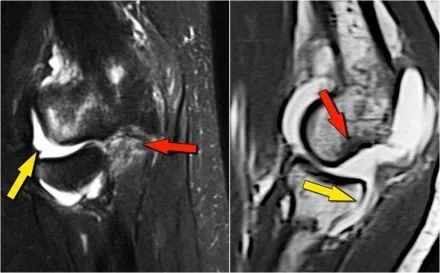

下面是一个不同的病人。请注意,这是一个年轻的病人,因为骨骺仍然开放。

外侧滑车(黄色箭头)有一个大的骨软骨病变。注意软骨下骨的水肿(红色箭头)。软骨仍然完好无损。